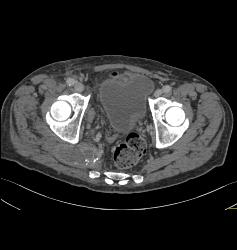

Iliac Artery Aneurysm With Iliopsoas Bleed